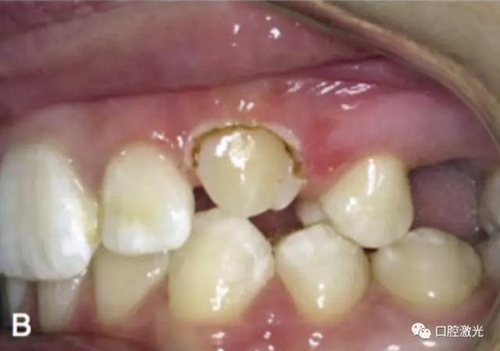

治療前

激光牙齦切割后即刻

粘接托槽

3周后效果